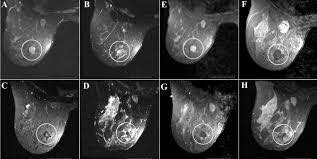

*SIÊU ÂM:nhanh rẻ chính xác, an toàn nhưng đòi hỏi tay nghề bs tốt.

Chụp nhũ ảnh : rất tốt, hình ảnh rõ ràng nhưng bs và kỹ thuật viên chụp phải có trình độ tốt.

Vì các bướu này không đau nên thường khi chẩn đoán, bác sĩ phải dựa trên việc sờ nắn và siêu âm. Ở những phụ nữ trên 30-35 tuổi, cần thêm các xét nghiệm khác nữa để hỗ trợ trong việc chẩn đoán phân biệt với u bọc sợi. Sau khi được chẩn đoán, các bác sĩ xem xét mức độ xâm lấn của khối u bằng cách chọc hút bằng kim để rút dịch nhằm thẩm định là u lành tính hay u ác tính.

Nói chung, khi được chẩn đoán bị bướu sợi tuyến vú, đừng quá lo lắng vì đây là một loại bướu lành và khi phẫu thuật bóc tách có thể tái lại tùy theo cơ địa mỗi người. Hiện tại nếu các bướu sợi tuyến < 2cm và không đau thì bác sĩ chỉ cần theo dõi bằng khám lâm sàng, siêu âm và nhũ ảnh khi đã xác định chính xác bằng sinh thiết nhờ kim nhỏ (FNAC).

Fibroadenomas that don’t grow and are definitely not cancerous can be closely monitored with clinical breast exams and imaging tests, such as mammograms and ultrasounds.